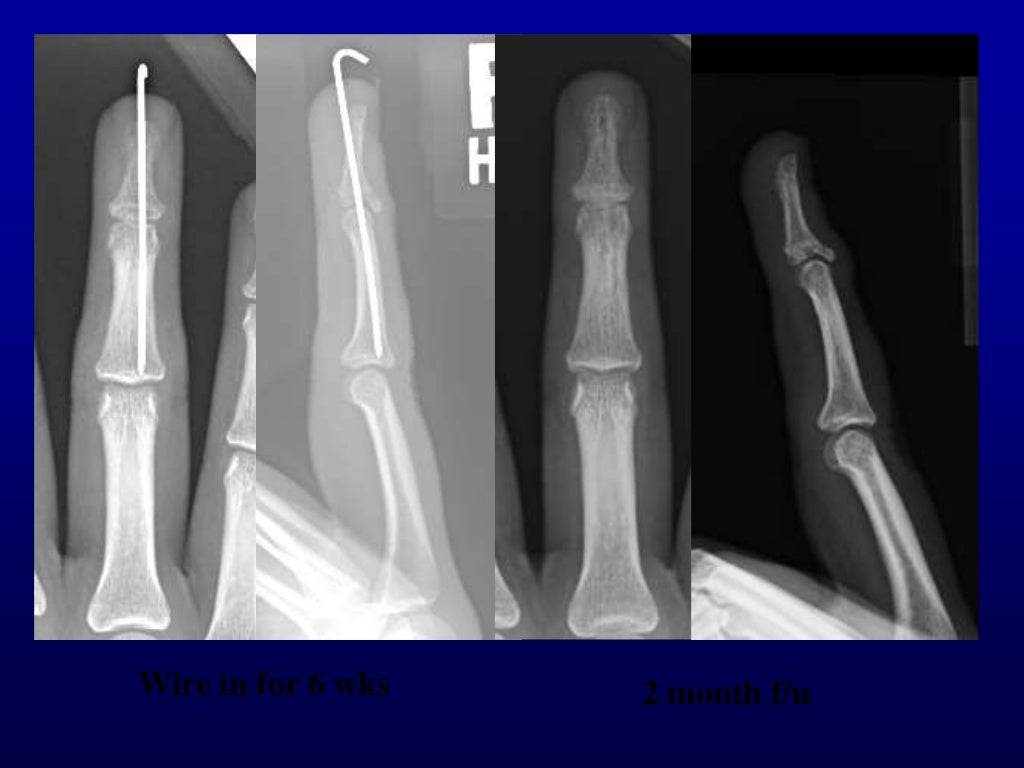

Percutaneous pin fixation of the mallet fracture, review of the techn… Pin Fixation In Fracture Pin hole greater than 1/3rd of the bone's diameter will substantially increase the risk of pinhole fracture after removal of the pin In fractures, the pins are typically. Highly consider ha pins for extended use and or definitive fracture care. Next, your surgeon will secure the pieces of your tibia or fibula to each other (fixation). Wires are often used. Pin Fixation In Fracture.

From www.slideshare.net

Percutaneous pin fixation of the mallet fracture, review of the techn… Pin Fixation In Fracture In fractures, the pins are typically. One method of changing the stability is to alter the pin configuration. Next, your surgeon will secure the pieces of your tibia or fibula to each other (fixation). Highly consider ha pins for extended use and or definitive fracture care. In many cases, they are used in conjunction. Pin hole greater than 1/3rd of. Pin Fixation In Fracture.

Percutaneous pin fixation of the mallet fracture, review of the techn… Pin Fixation In Fracture In many cases, they are used in conjunction. Highly consider ha pins for extended use and or definitive fracture care. In fractures, the pins are typically. External fixation is accomplished by placing pins or screws into the bone at various points. Wires are often used to pin the bones back together. One method of changing the stability is to alter. Pin Fixation In Fracture.